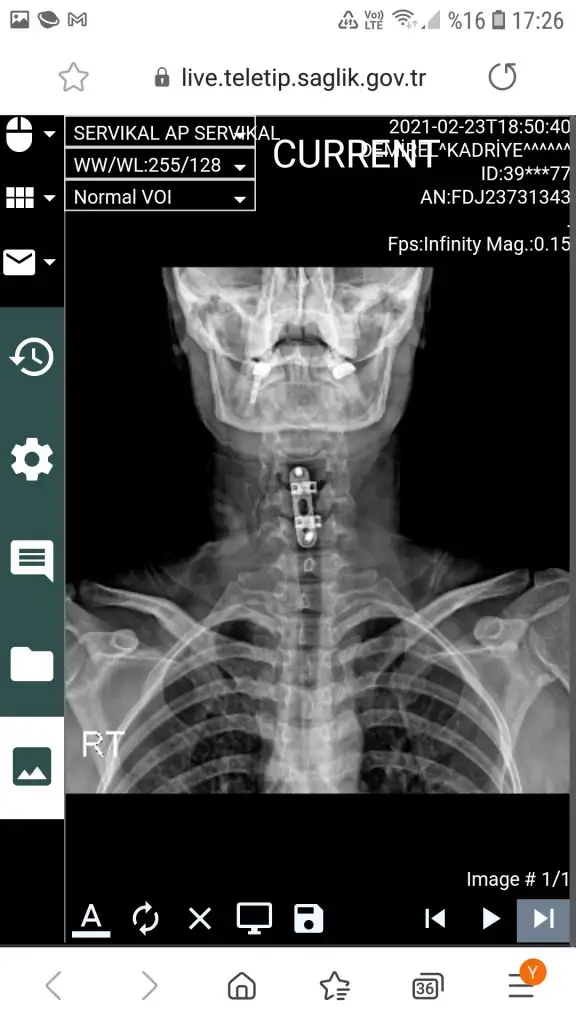

kızlar merhaba ben 20 gün önce oldum boyun fıtığı ameliyatını canım takılan protezin kayma şansı yok o kaynayana kadar asıl olay ameliyat olmaya kara verdiğinde başlıyor. Benim 4 tane fıtığım var 1 tanesi 5 senedir omuriliğime basıyordu ama benim pek şikayetim yoktu, gece seneden bu yana sonuçlarım zaten ameliyattı, ameliyattan başkada yapılacak bişey yoktu. Benim sonuçlarıma bakan doktorlar inanamıyordu hatta gecen sene senin ya sedyede yada ölüyorum diye gelmen gerek bu sonuçlarla dedi doktorum.

Bana ameliyattan başka yapılacak birşey olmadığını her doktor söyledi aklına gelen bütün hastanelere gittim. Açık konuşmak gerekirse felç başlayınca olurum dedim doktorlarda onaylamıştı çünkü şikayetim yoktu. Bu sene omuriliğimde zedelenme başlamıştı sağ tarafımda sinir zedelenmelerinden felçte başlamış ama ben farketmedim bile sadece senelik kontrole gitmiştim. Ameliyatımı oldum hiç bir şikayetim yok boyunluk takmak haricinde çünkü tahriş oldu boynum malesef. 2 ayrı yöntem var ameliyat olmak istediğin zaman önemli olan hangisine karar vereceğin. Biri disk protez diğeri füzyon.

Canım fıtıklarımız aynı c5-c6dan ameliyat oldum. C2-C3 tede var o ufak benim diğer 2 fıtığım başka yerlerde bendede toplam 4 tane var yani 3 kaldı.

2 ayrı yöntem var biri disk protez diğeride kemik tozu dediğin füzyon. Canım şöyle anlatayım ben yönteme karar vermek için 20 gün dolandım kemik tozu dediklerini bi protez var o takılıyor onun içinde boşluk var kemik tozu veya benzeri şeylerle kemiklerin birbirine kaynaması sağlanıyor, gerçek kemik bu protezler bulunmadan önce kalçadan alınıp takılıyormuş artık yapan yok gerekte yok zaten. Bu yöntemle %7 hareket kısıtlaman oluyor kafanı sağa sola yukarı aşağıya %7 çeviremiyorsun. Doktorlar farketmezsin çok fazla diyor aynı protezden 2 yada 3 tane takılcakki o zaman farkedersin zaten o zamanda kafayı pek oynatamazsın zaten. Diğer yöntem harika disk protez hiç bir hareket kısıtlaması yok boyunluk bile takmak zorunda kalmıyorsun ameliyattan sonra ama 8-10 yıldır kullanılan bir yöntem bu ve gelecekte ne olacağı bilinmiyor. Yorulma ömrü 15-20 yılmış yani 15-20 yıl sonra %90 değiştirilmesi gerekecek belki içinde kırılacak allah korusun genç olduğumuz için bazısı kesin bu yöntem diyor bazısı asıl gençsin diye kesinlikle olmaz diyor. Canım ben ve eşim makina mühendisiyiz oturup doktorlarlada herşeyini inceledik boynumuza yüklenecek yük parçanın yorulma ömrüydü şuydu buydu mekanik kısımları biz füzyona karar verdik en azından ömürlük çözüm bi daha aynı yerde sıkıntı olmayacak sadece biraz hareket kısıtlılığı olacak. Disk protezde birde şu var kemik deforme oluyor, 2. ameliyat çok daha fazla riskli ve aynı yöntemi bi dahada kullanamazsın bence 2 omuruna zarar vermiş olcaksın çıkarttıklarında.

Bizim doktorumuz platin önermiyor..

Kayma yapar,yabancı cisim çabuk kaynamaz problem çıkarır ben koymam dedi..

Sana anlattığım gibi vidalama yöntemi uyguladı..

Merheba ben 39 yaşındayım benimde iki fıtığım var c5 ve c6 sol tarafta sağ tarafımda da kireçlenme oluşmuş oldukça büyük fıtıklarımın olduğu söylendi ameliyat dendi benim şikayetim kollarımda çabuk yorulma boynumda ağrı el parmaklarımda ağrı, güç kaybım yoktu ameliyatı kabul ettim onayladım 10 gün oldu ameliyat olalı ,ben hızlı toparlandım ameliyat sonrası en çok yutkunurken olan boğazda ağrı beni çok zorladı tükürüğümü bile çok zor yuttum yutkunma hissi gelicek diye ödüm kopuyordu ama neyseki 4 gün sürdü bu zorlanma şimdi çok şükür iyiyim ben hemen ayağa kalktım dışarı çıktım bakkala markete parka her yere gittim birazda tez canlıyım bide benim acı eşiğim yüksek fazla ay ay ay oy oy oy yapmadım makinaya çamaşır attım astım vs kısacası bir kaç gün içinde toparlandım 2 gün dür ağrı kesici içmiyorum ve sadece ağrı kesici olarak parol kullandım ameliyatım 3 buçuk saat sürdü hastanede 2 gün kaldım 2 pilak takıldı sağ tarafımdaki kireçlenmede kazındı artık hiç fıtığım kalmadı şimdilik iyi gidiyo sonrasını zamanla görücem bide ben boyunluğumu yatarkende hiç çıkartmadım ameliyat boynumun sağ ön taraftan yapıldı gece yatarken yüksek yastık ve sol yan tarafıma rahat yattım korkulacak bişey yok artık tıp çok ilerledi ne kadar çok sorup araştırırsanız okadar çok kafanız karışır şimdilik yaşadıklarım bukadar merak ettikleriniz olursa cvp larım.